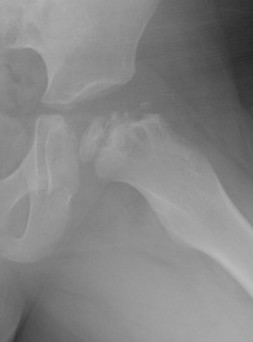

Valgus femoral osteotomy

Concept

Hinge abduction

- move medial, better-preserved part of the femoral head into the loading zone

- reduce adduction contracture and distalize the greater trochanter